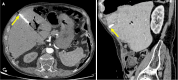

Endoscopic retrograde cholangiopancreatography (ERCP) is a cornerstone procedure for the diagnosis and management of pancreatic and hepatobiliary diseases. Although its diagnostic role has been increasingly supplanted by noninvasive imaging modalities such as magnetic resonance imaging (MRI) and magnetic resonance cholangiopancreatography, the therapeutic applications of ERCP have continued to expand. ERCP is widely used and has a generally favorable safety profile. However, it is important to recognize expected post-procedural imaging findings and serious complications that can arise. The increasing complexity of therapeutic interventions and the growing volume of procedures have led to a higher incidence of complications that often present with overlapping clinical and laboratory features, underscoring the critical role of imaging in differential diagnosis. This review focused on the typical normal ERCP findings and the imaging characteristics of common complications, including pancreatitis, bleeding, ERCP-related infections, perforations, and stent-related complications. Computed tomography (CT) is particularly valuable in timely recognition, management, and surgical decision-making for these complications. Furthermore, MRI offers a radiation-free alternative for managing complications in selected patients. Therefore, radiological modalities, particularly CT and MRI, are critical tools for the rapid diagnosis, management, and surgical decision-making processes for post-ERCP complications.